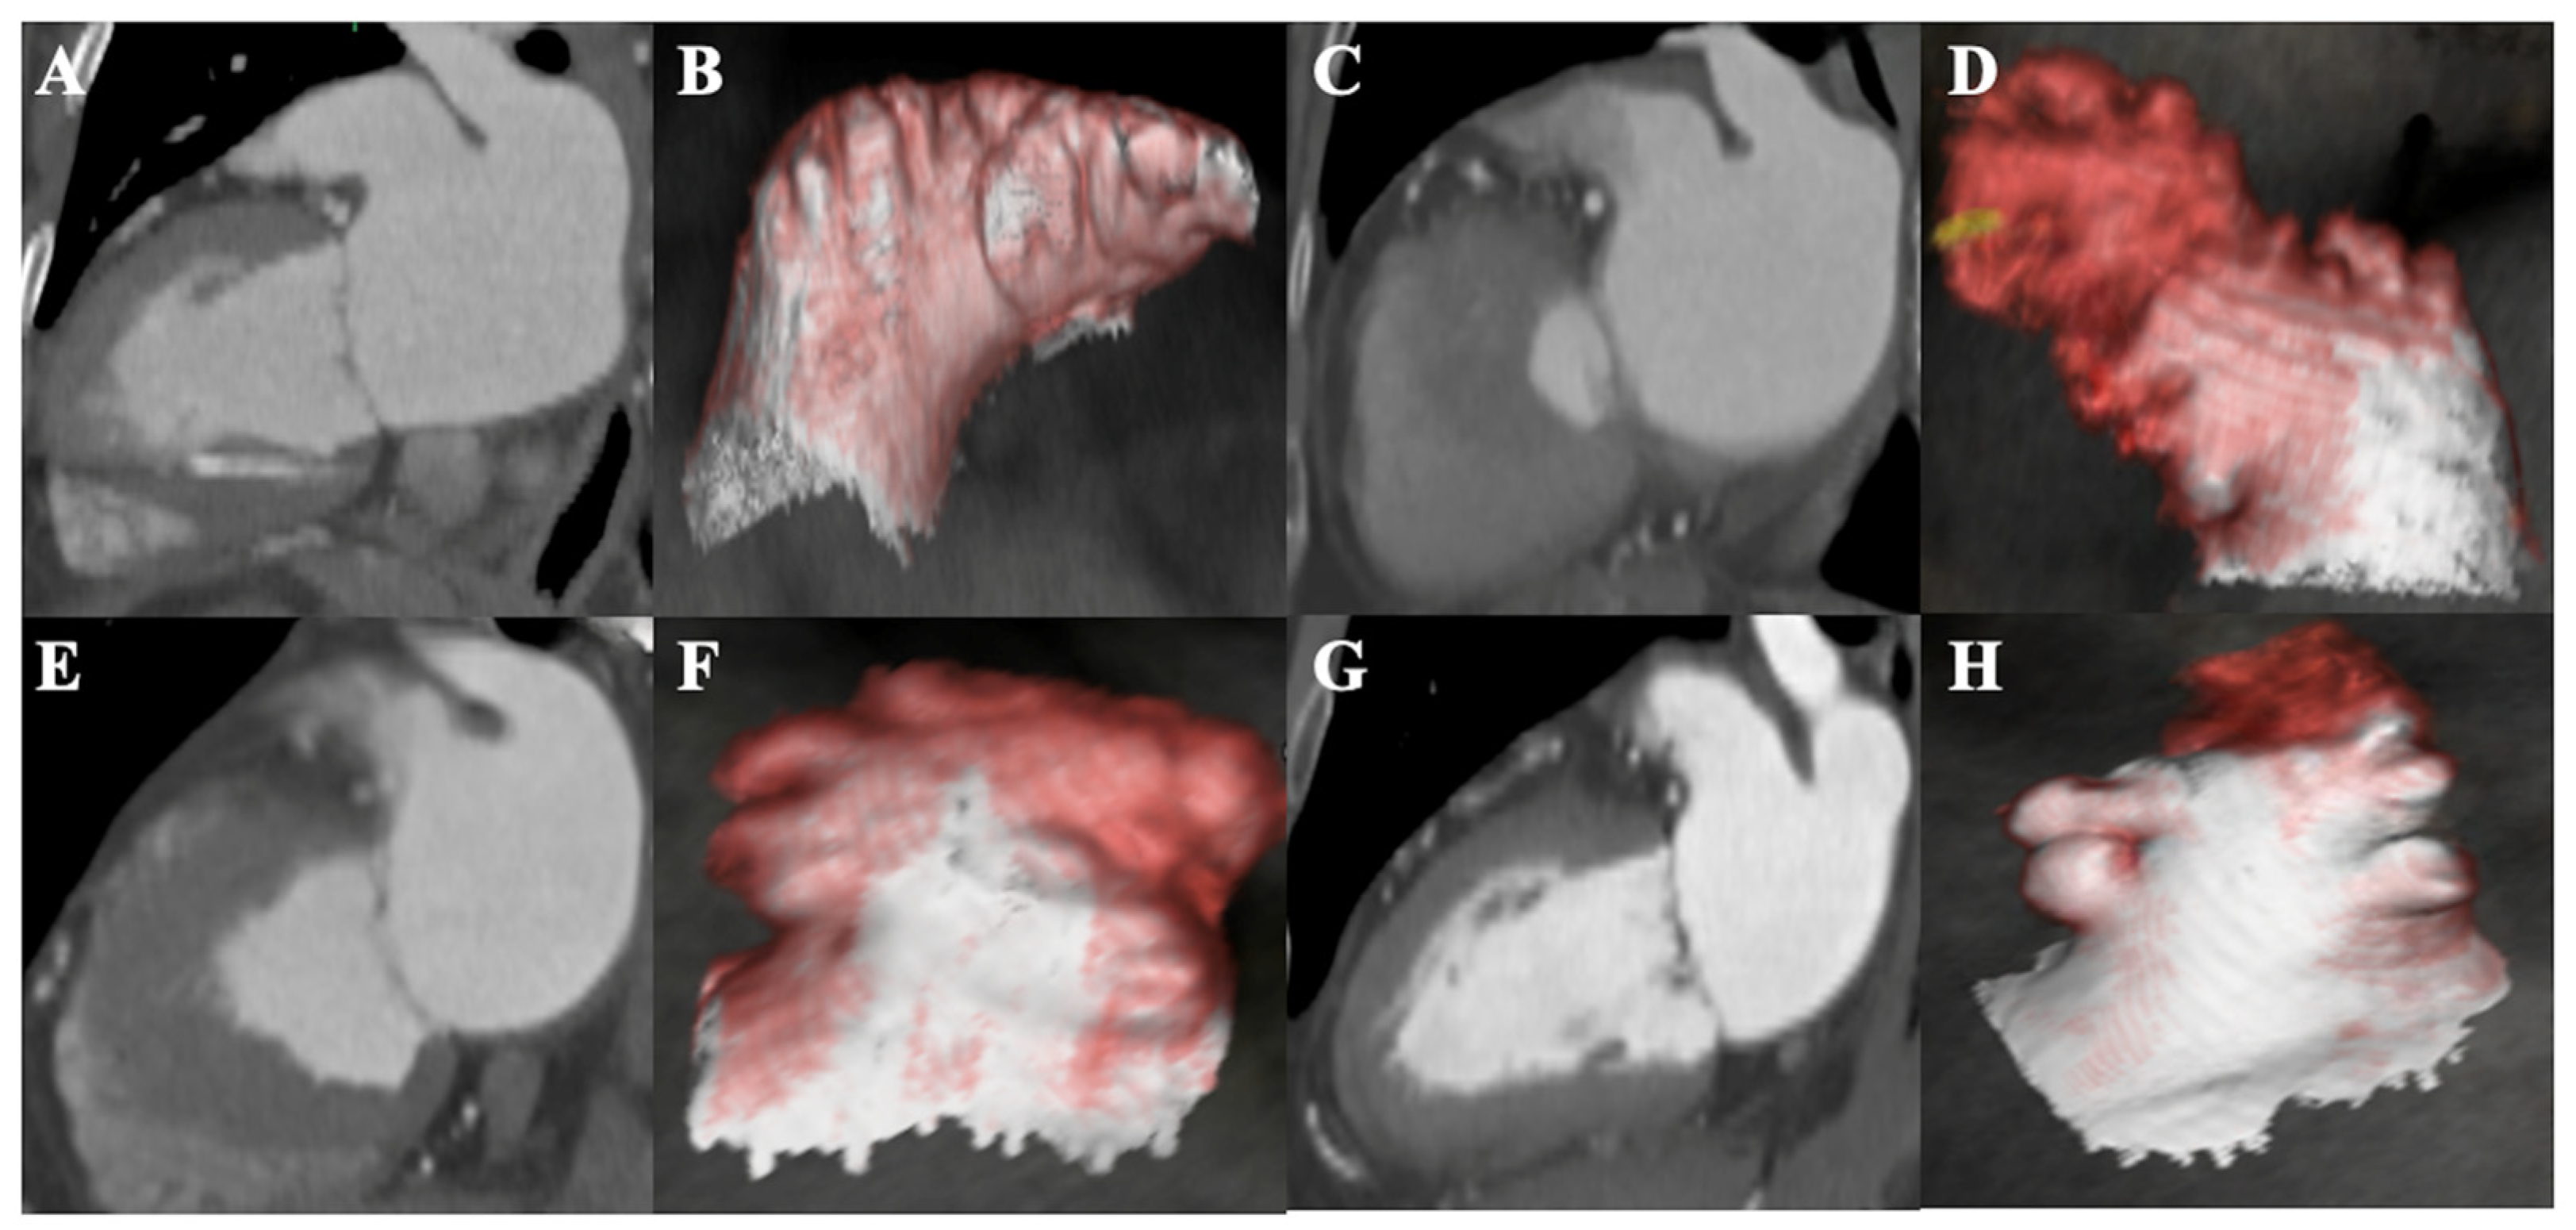

2.2. LAA Morphology and Imaging Analysis